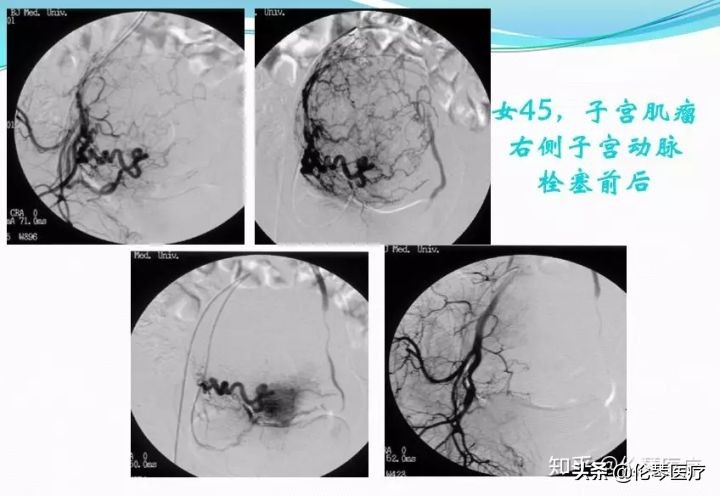

这也是一个非常典型的子宫肌瘤患者,45岁,右侧子宫动脉栓塞前后的对比图片。我们直接插管到子宫动脉以后,右侧子宫动脉做的造影,显示一个巨大的肌瘤。切除巨大的肌瘤以后,我们给她做栓塞治疗,栓塞治疗以后子宫肌瘤的动脉未见明确显示。

在磁共振上面,一个巨大的肿块——子宫肌瘤,大家可以明确看出子宫肌瘤栓塞术前术后的变化,子宫肌瘤明显缩小,部分引起坏死。